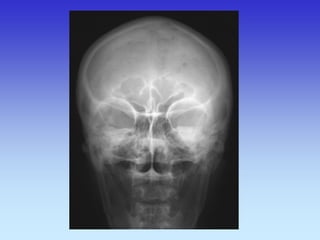

SINUSI PA snimka

1.Nosna pregrada

2.Frontalni sinus

3.Maksilarni sinus

4.Etmoidni sinus

KOSTI LICA 1. Frontalni sinus 2. Etmoidni sinus 3. Koštani dio nosne pregrade 4. zigomatično-frontalna sutura 5. Maksilarni sinus 6. Zigomatična kost 7. Zigomatični luk 8. Mandibula 9. Donji rub orbite 10. Lijeva orbita